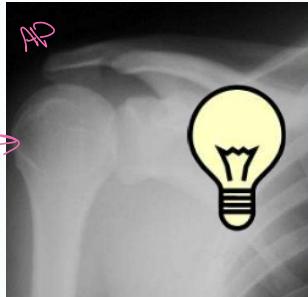

X-ray Findings:

- AP view:

- The humeral head is medially rotated → “Electric light bulb” sign